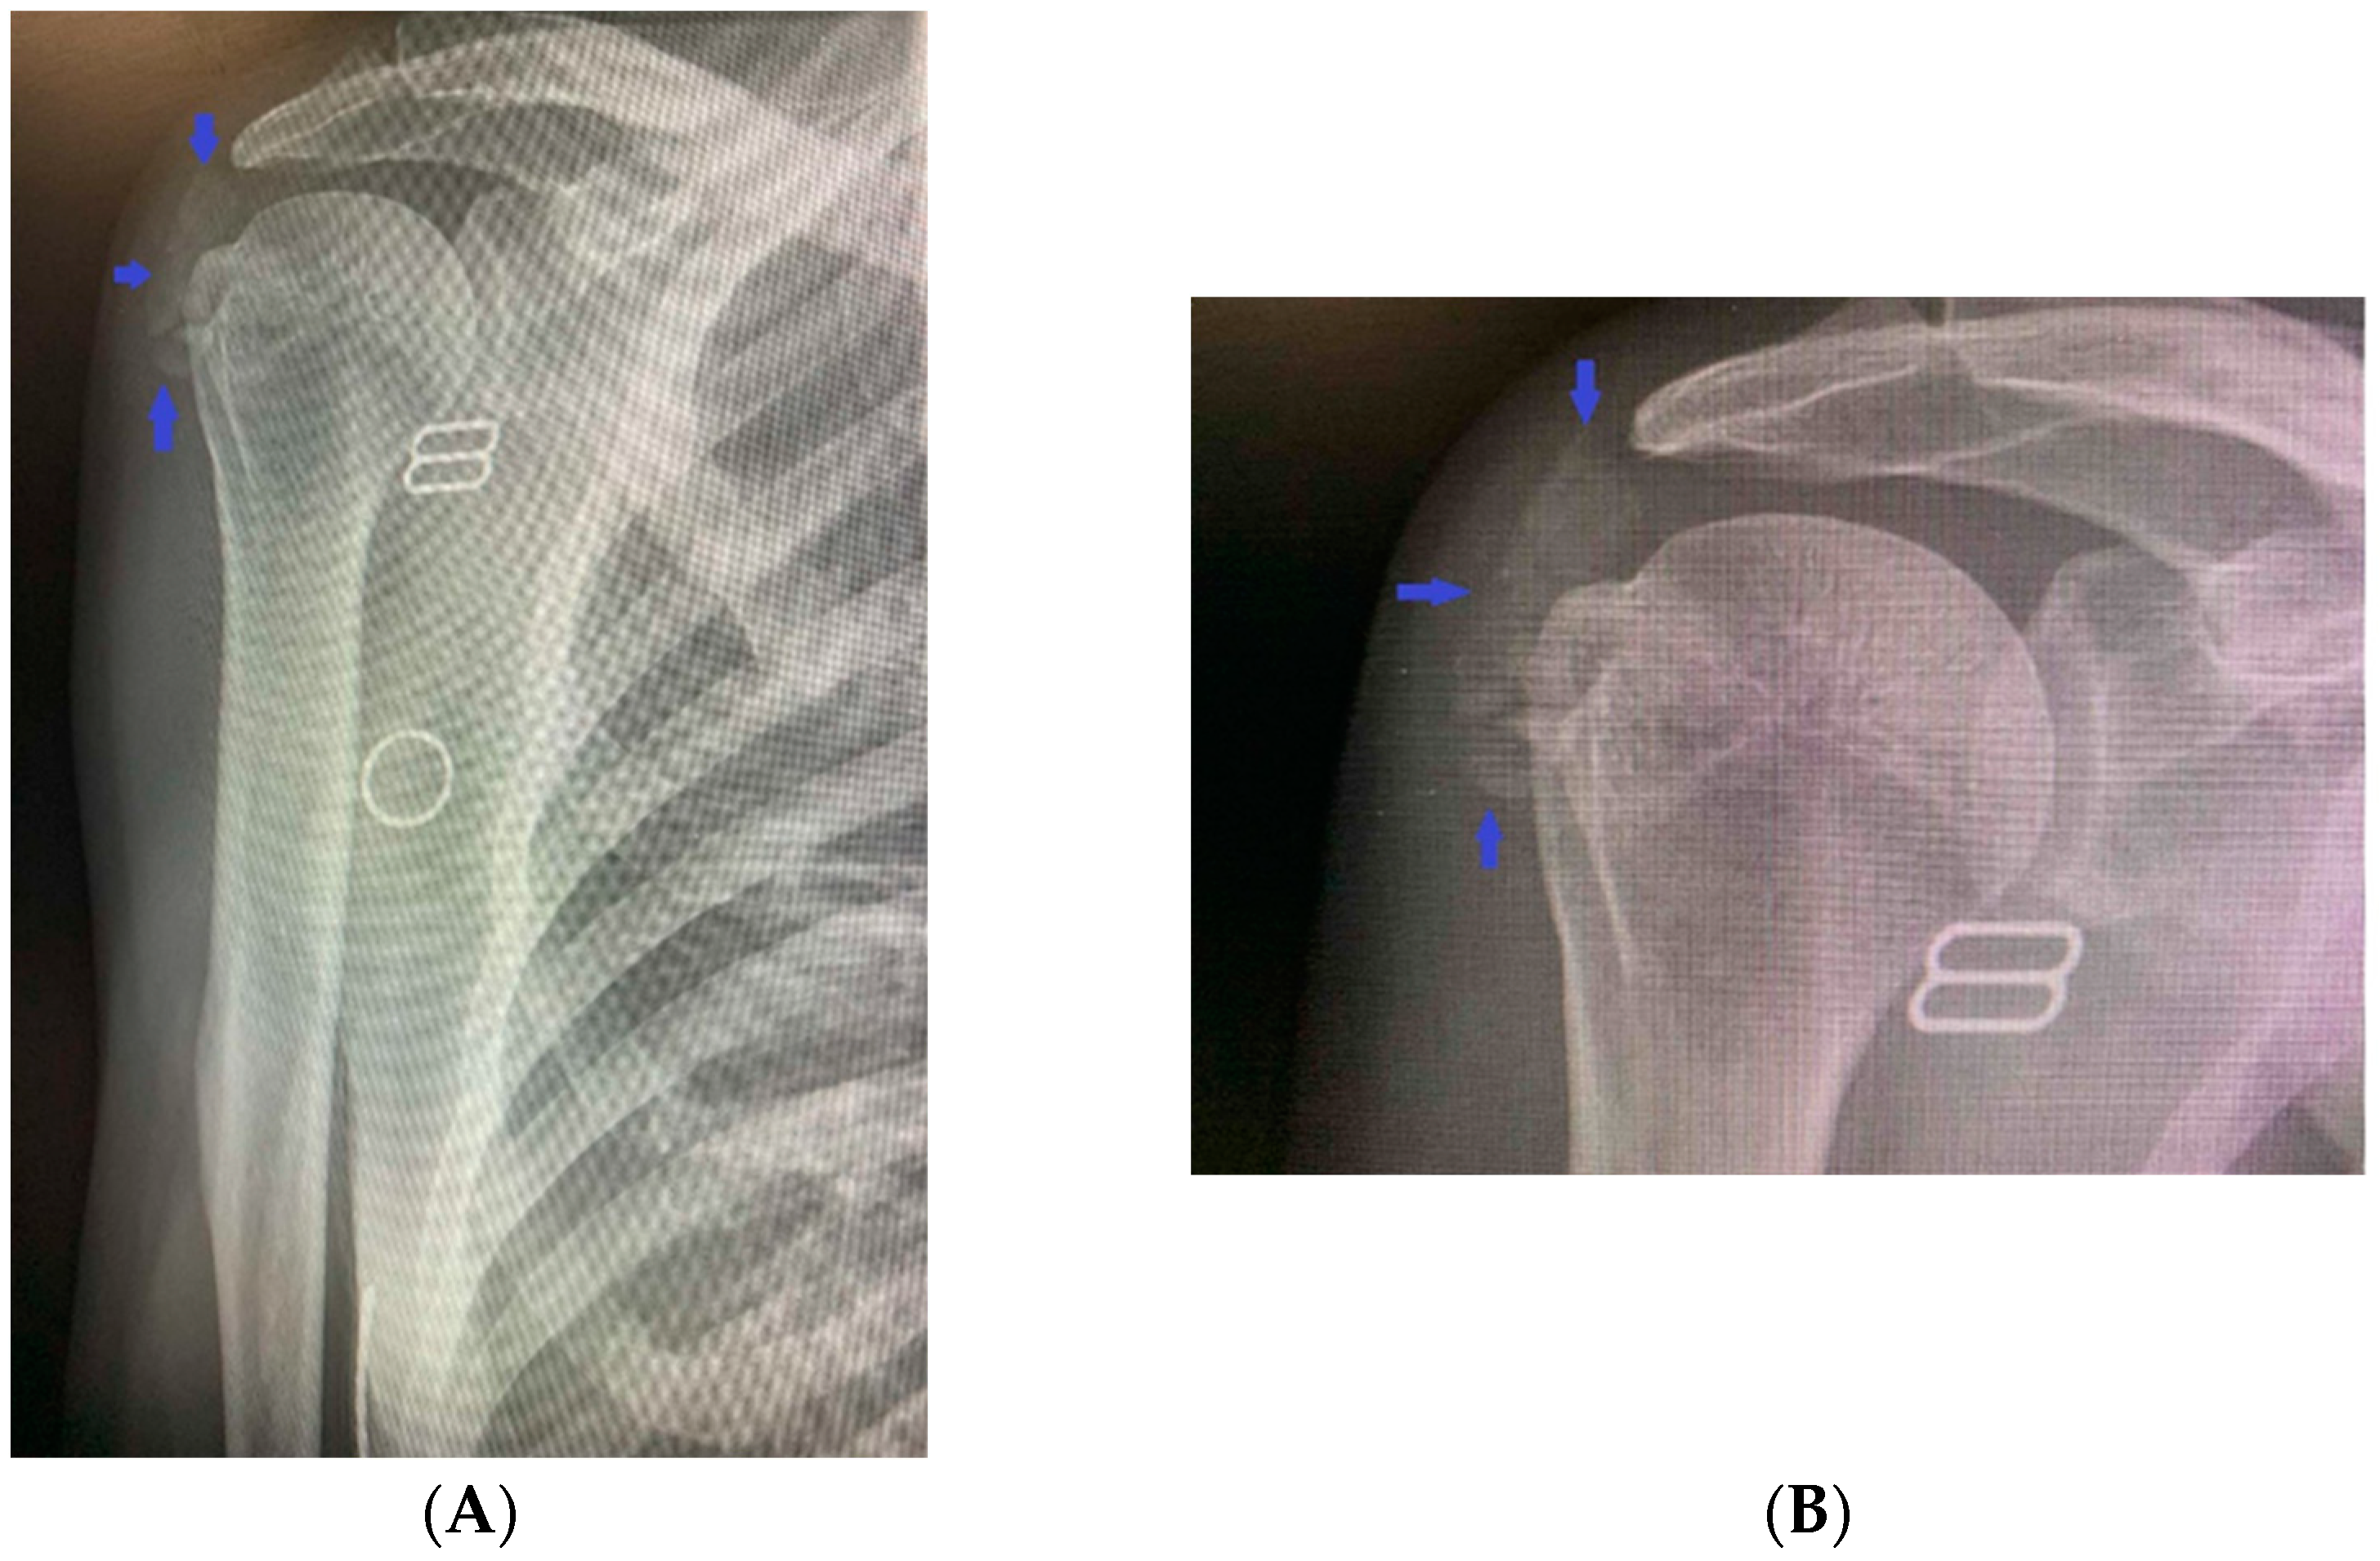

Additionally, there was functional, palpable discomfort, along with movement limitations. The general physical status did not show any pathological abnormalities. Biochemical tests confirmed the previous findings of disturbances in the phosphorus metabolism of the patient: hyperphosphatemia (2.27 mmol/L, normal range 0.77–1.36 mmol/L), reduced 24 h urinary excretion (9.2 mmol/L, normal range 10.9–32.3 mmol/L), low 24 h phosphate clearance (0.08 mL/s, normal range 0.140–0.151 mL/s), increased tubular reabsorption (94.1%), and normal levels of total calcium (2.41 mmol/L, normal range 2.15–2.5 mmol/L) and ionized calcium (1.28 mmol/L, normal range 1.16–1.31 mmol/L), 24 h urinary excretion (3.7 mmol/L, normal range 2.5–7.5 mmol/L), 1.25 (OH) vitamin D3 (57 ng/mL, recommended levels above 50 ng/mL), and parathyroid hormone (31.1 pg/mL, normal range 12–88 pg/mL). An X-ray of the shoulder joint showed calcium deposits in the surrounding soft tissues (Figure 2A,B).

Figure 2.

(A,B) An X-ray of the right shoulder joint revealing calcium deposits in the surrounding soft tissues.

A hetero-dense cloud-like lesion measuring 5.22 × 1.87 cm with soft-tissue and calcium-equivalent densitometric density was seen in the right deltoid muscle at the level of the clavicle and lateral to the right humeral head, without involving neighboring bones and structures, according to spiral computed tomography with 3D reconstruction (Figure 3A,B).

Figure 3.

(A,B) Computed tomography with 3D reconstruction showing cloud-like lesion with soft-tissue and calcium-equivalent densitometric density in the right deltoid muscle lateral to the right humeral head and not involving adjacent bones and structures.